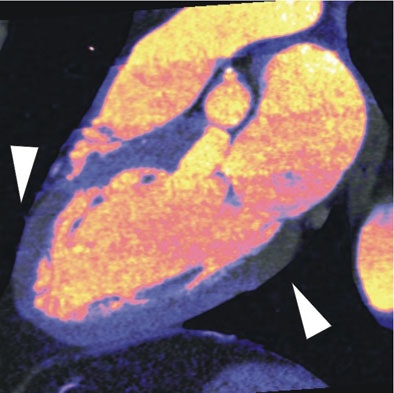

| In a 64-year-old man with chest pain, colored regions of blood-pool images represent iodine, while the darker parts of the myocardium depict ischemia as a lack of contrast uptake. Arrows indicate the myocardial blood-pool deficit, i.e., ischemia. |

| In a 64-year-old man with chest pain, image of the corresponding slice shows inferior ischemia (arrows). |